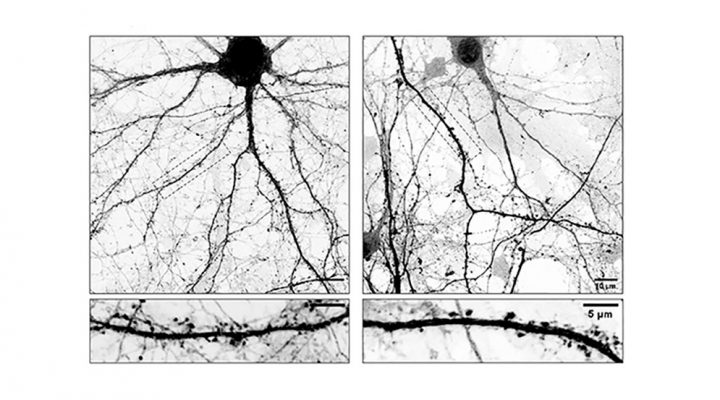

Estudio preclínico: la estimulación con luz y sonido intermitentes promueve el desarrollo de nuevas neuronas en cerebros envejecidos